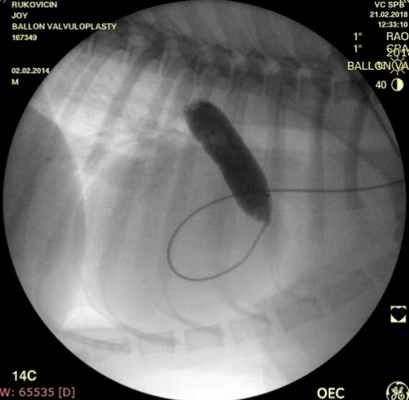

Показанием к оперативному лечению служит градиент систоличесокого давления на клапане легочной артерии свыше 50 мм рт.ст. При наличии дисплазии створок клапана — показана хирургическая коррекция порока, в остальных случаях возможно эндоваскулярное лечение. Операция выполняется в большинстве случаев под в/в анестезией, за исключением новорожденных, находящихся в критическом состоянии, у которых операция выполняется пол общим обезболиванием. Суть операции заключается в том, что после пункции бедренной вены в полость правого желудочка проводится и устанавливается катетер, далее проводник через клапан легочной артерии проводится в дистальные отделы легочной артерии. По проводнику в последующем проводится баллонный катетер и выполняется вальвулопластика. В настоящее время операция не сопровождается развитием летальных исходов и осложнений. Госпитальный период ограничен 3 днями.

Проведено: баллонная вальвулопластика клапана легочной артерии (Тип А). Баллон Cordis maxi 40х20 мм. Инфляция до 5 атм. 10 попыток.

ЭхоКГ (после операции): ГД (градиент давления) на ЛА (легочной артерии) - 39 мм.рт.ст. РКЛА (регургитация клапана легочной артерии) – ср. - 16 мм рт.ст. Геометрия сердца не нарушена. Выраженное снижение градиента давления после баллонной дилатации КЛА (клапана легочной артерии) на 55%.